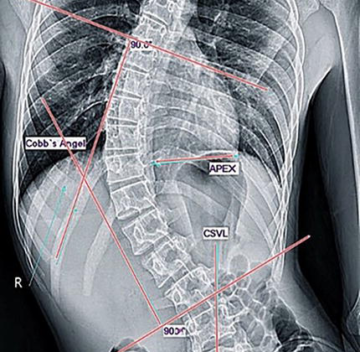

أبريل 25, 2026 أهم العوامل التي تؤثر على تصحيح دوران الفقرات داخل حزام اعوجاج العمود الفقري… scoliosis, اعوجاج العمود الفقري, الجنف لا يوجد تعليق 14 المشاهدات أهم العوامل التي تؤثر على تصحيح دوران الفقرات داخل حزام اعوجاج العمود الفقري مقدمة: لماذا نهتم بدوران الفقرات في اعوجاج العمود الفقري؟ يُعد اعوجاج العمود الفقري عند المراهقين حالة معقدة لا تؤثر فقط على